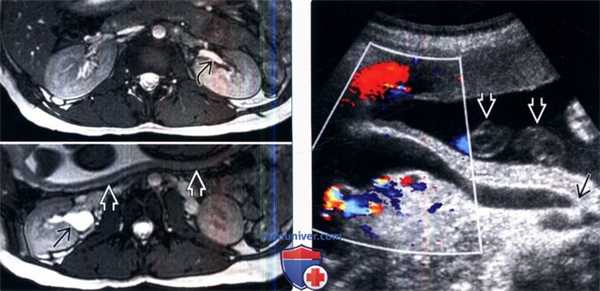

(Слева) МРТ, выполненная для исследования плода, Т2-ВИ, аксиальный срез: случайно выявленное небольшое расширение собирательной системы матери справа, которое распространяется до входа в малый таз. Собирательная система слева не изменена. Обратите внимание на заднюю стенку матки.

(Справа) Цветовая допплерография правой почки в продольной плоскости: значительное расширение мочеточника. Мочеточник сужается в месте, где он пересекает подвздошные сосуды. Уретерэктазия чаще встречается справа. Обратите внимание на петли пуповины.